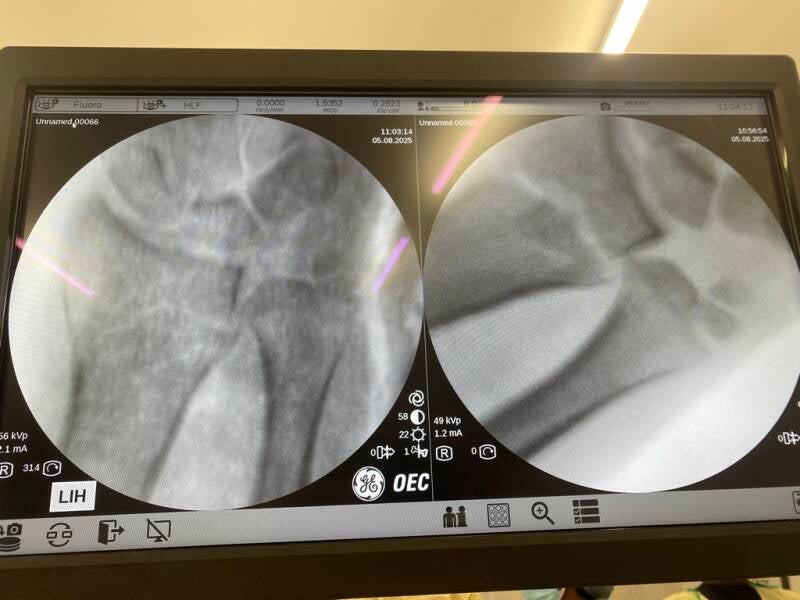

Everything goes like clockwork. Patricia drifts off to sleep. Ketamine and inhalational gases on board. Keith holds Patricia’s hand firmly. James applies an equal and opposite tractional force from Patricia’s elbow. The wrist reduces beautifully. The dinner fork again matches the set. Normal shape appears. An x-ray from Elvis confirms perfect positioning. James’ team applies plaster of Paris. The plaster sets quickly. After 5 minutes Elvis gives a second magic image. All set. Patricia is allowed to wake up. After 15 minutes of fame. Or should I say 15 minutes of drug induced torpor? Isoflurane gas now switched off. Patricia slowly rouses. Practically pain free and all set to safari again.

Before and after pictures. Working with Xray vision